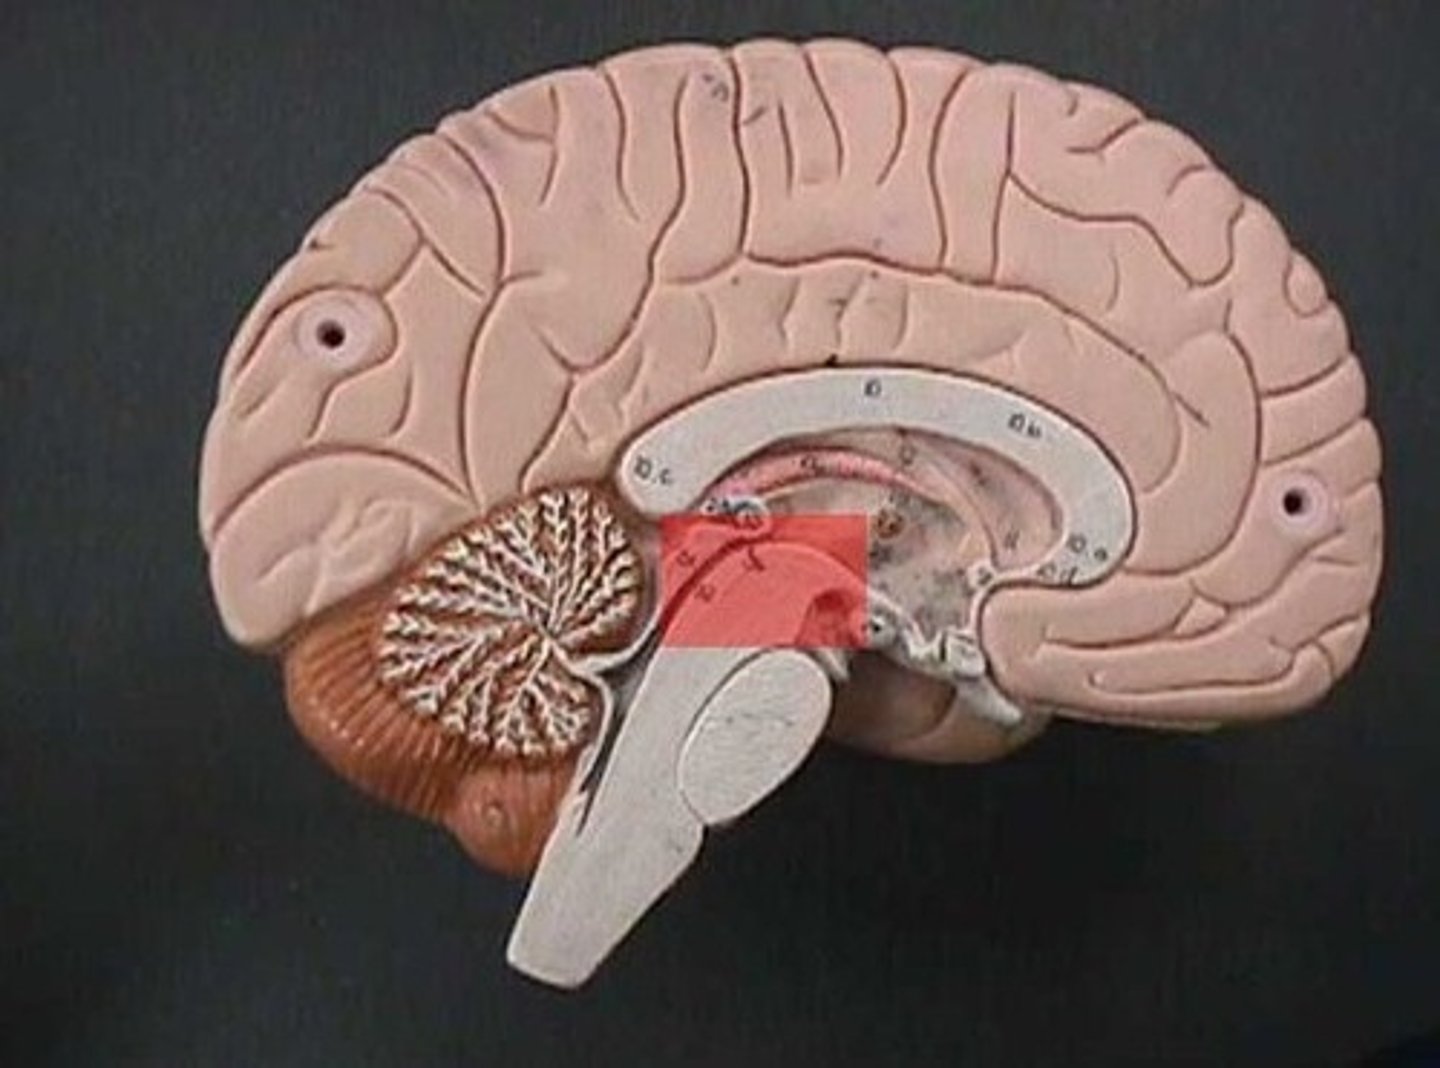

tentorium cerebelli

2nd largest, crescent-shaped, separates cerebrum (occipital lobes) from cerebellum (arrow #5)

has pons, cerebrellum, and upper part of the 4th ventricle

Cerebellum

posterior part of the brain that coordinates muscle movements and maintains balance

pons

center structure of the brain stem, located between the midbrain and the medulla oblongata

midbrain

or mesencephalon extends from pons to diencephalon. the pons is the center structure of the brain stem, located between the midbrain and the medulla oblongata